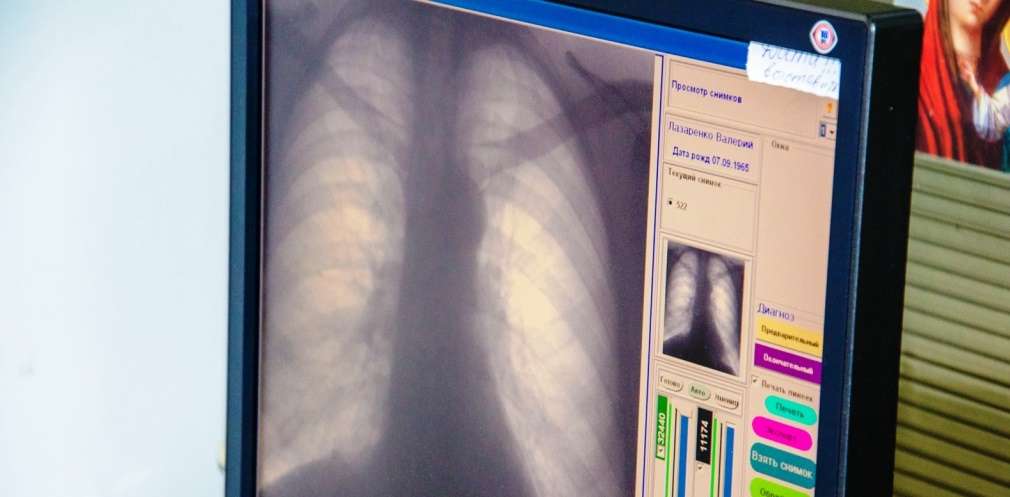

Для профілактики хвороби, слід вести здоровий спосіб життя, дотримуватися правил особистої гігієни та правильно харчуватися. Дітям потрібно вчасно робити вакцинацію, дорослим – раз на рік проходити флюорографію.